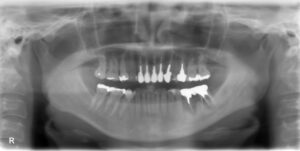

下顎大臼歯2本欠損症例

BEFORE AFTER 47歳女性/下2本欠損/インプラント埋込手術 【治療内容】 左下ブリッチの土台となる歯が欠けて…